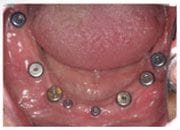

植入植體